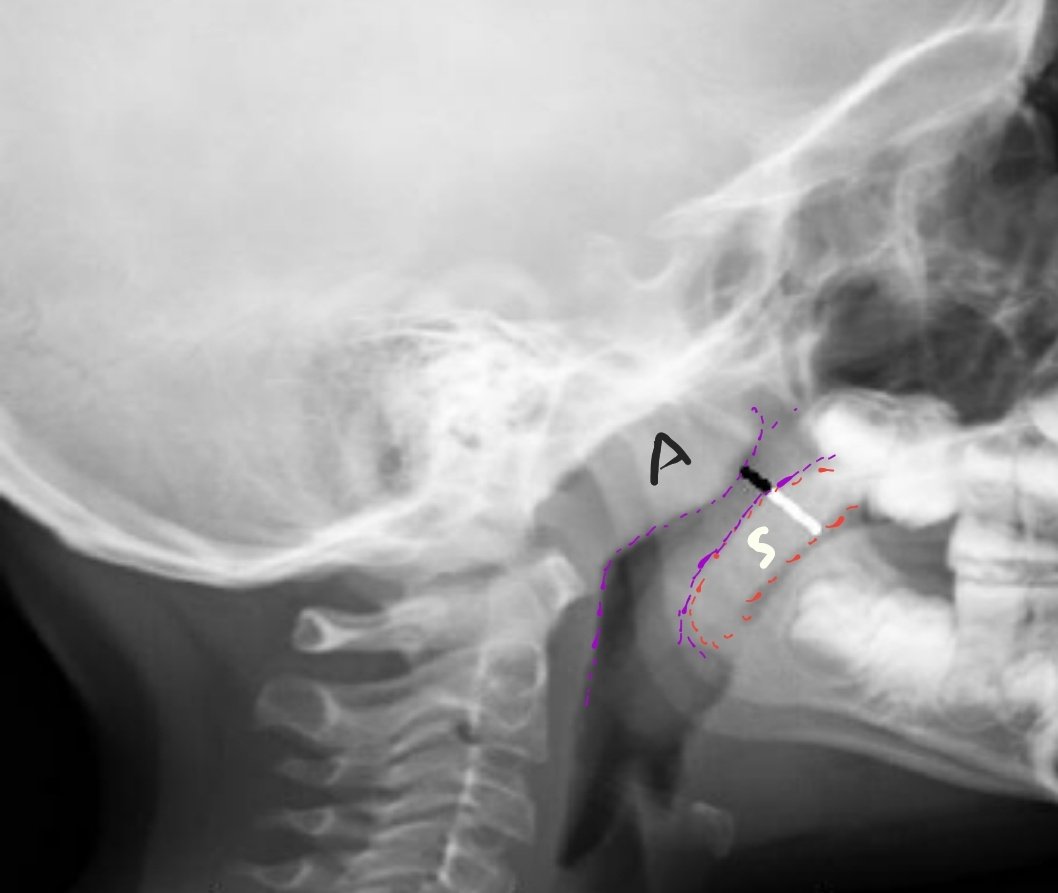

☆٣ فحص العنق(البلعوم-الحنجرة)

Nasopharynx

معلومات:

•{من أسهل الفحوصات وأكثرها أخطاء}.

•يطلب هذا الفحص من قبل أطباء الأنف والأذن و الحنجرة ENT،

وذلك لتقييم وجود أي تضخم في الزائدة/لحمية الأنف (adenoid) أو

اللوزتان (tonsils) تتسبب في تضيق مجرى الهواء عند الأطفال.

مثال لتضخمها

الوضع/

•وضع التصوير جانبي lateral.

•مسافة الأنبوب 150cm.

•تنبيه الطفل(٦سنوات غالباً) بعدم البلع.

•¤رفع الفك قليلاً حتى لا يحجب التشريح الذي نريدرؤيته¤.

•يبقي الطفل فمه مغلقاً ولاداع لفتحه(البحث المرفق)

عوامل التصوير:

نحن نصور أنسجة رخوة soft tissue

لذلك لابد من تقليل kV

¤يعد تقليل kVP من أهم النقاط بعد رفع الذقن قليلاً،

لأننا نريد رؤية جميع تفاصيل الأنسجة الرخوة في تلك المنطقة.¤

حيث يقوم الطبيب بالقيام بأحد طرق قياس مجرى الهواء ومعرفة مدى تضيقة

وهي نسبة

nasopharyngeal airway/soft palate (NA/SP)

نسبة عرض الخط الأسود إلى الخط الأبيض.